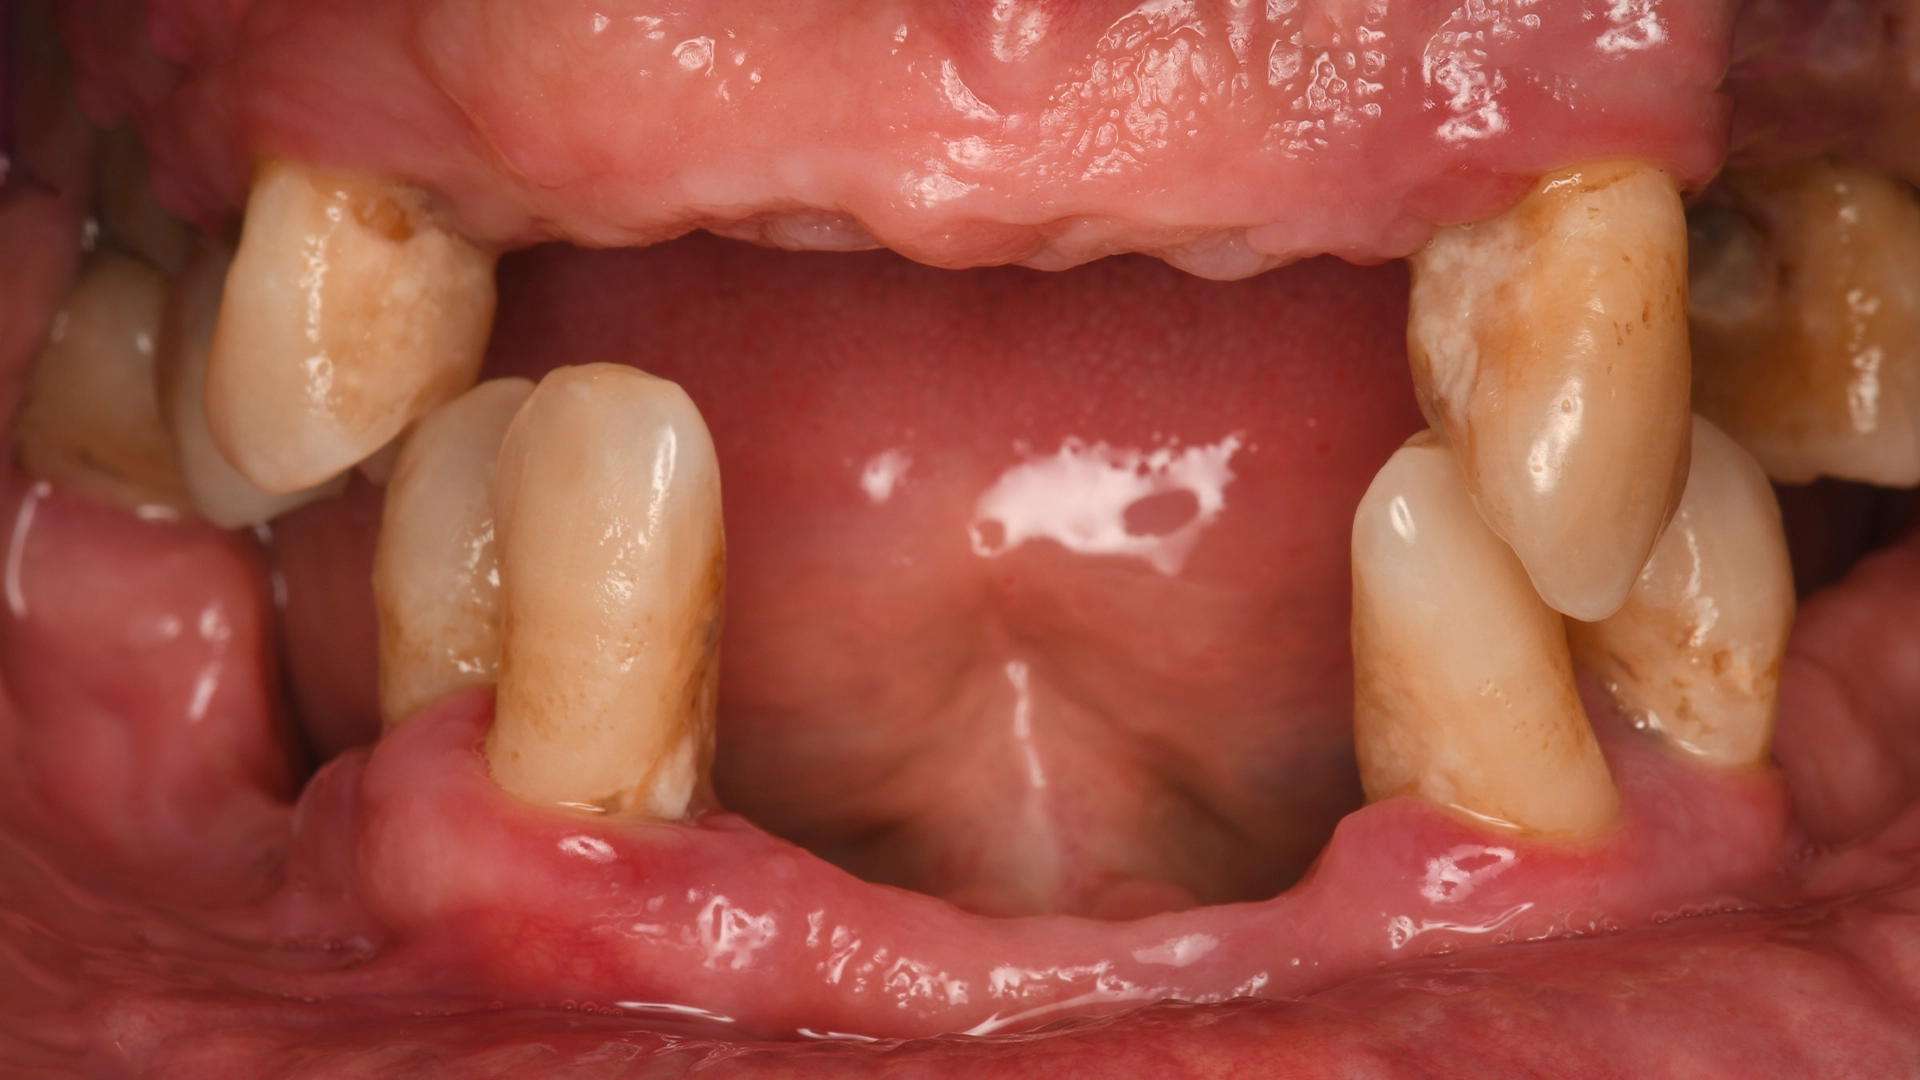

Before dental implant – missing or damaged teeth

Before After

Before dental implant – teeth needing implant evaluation